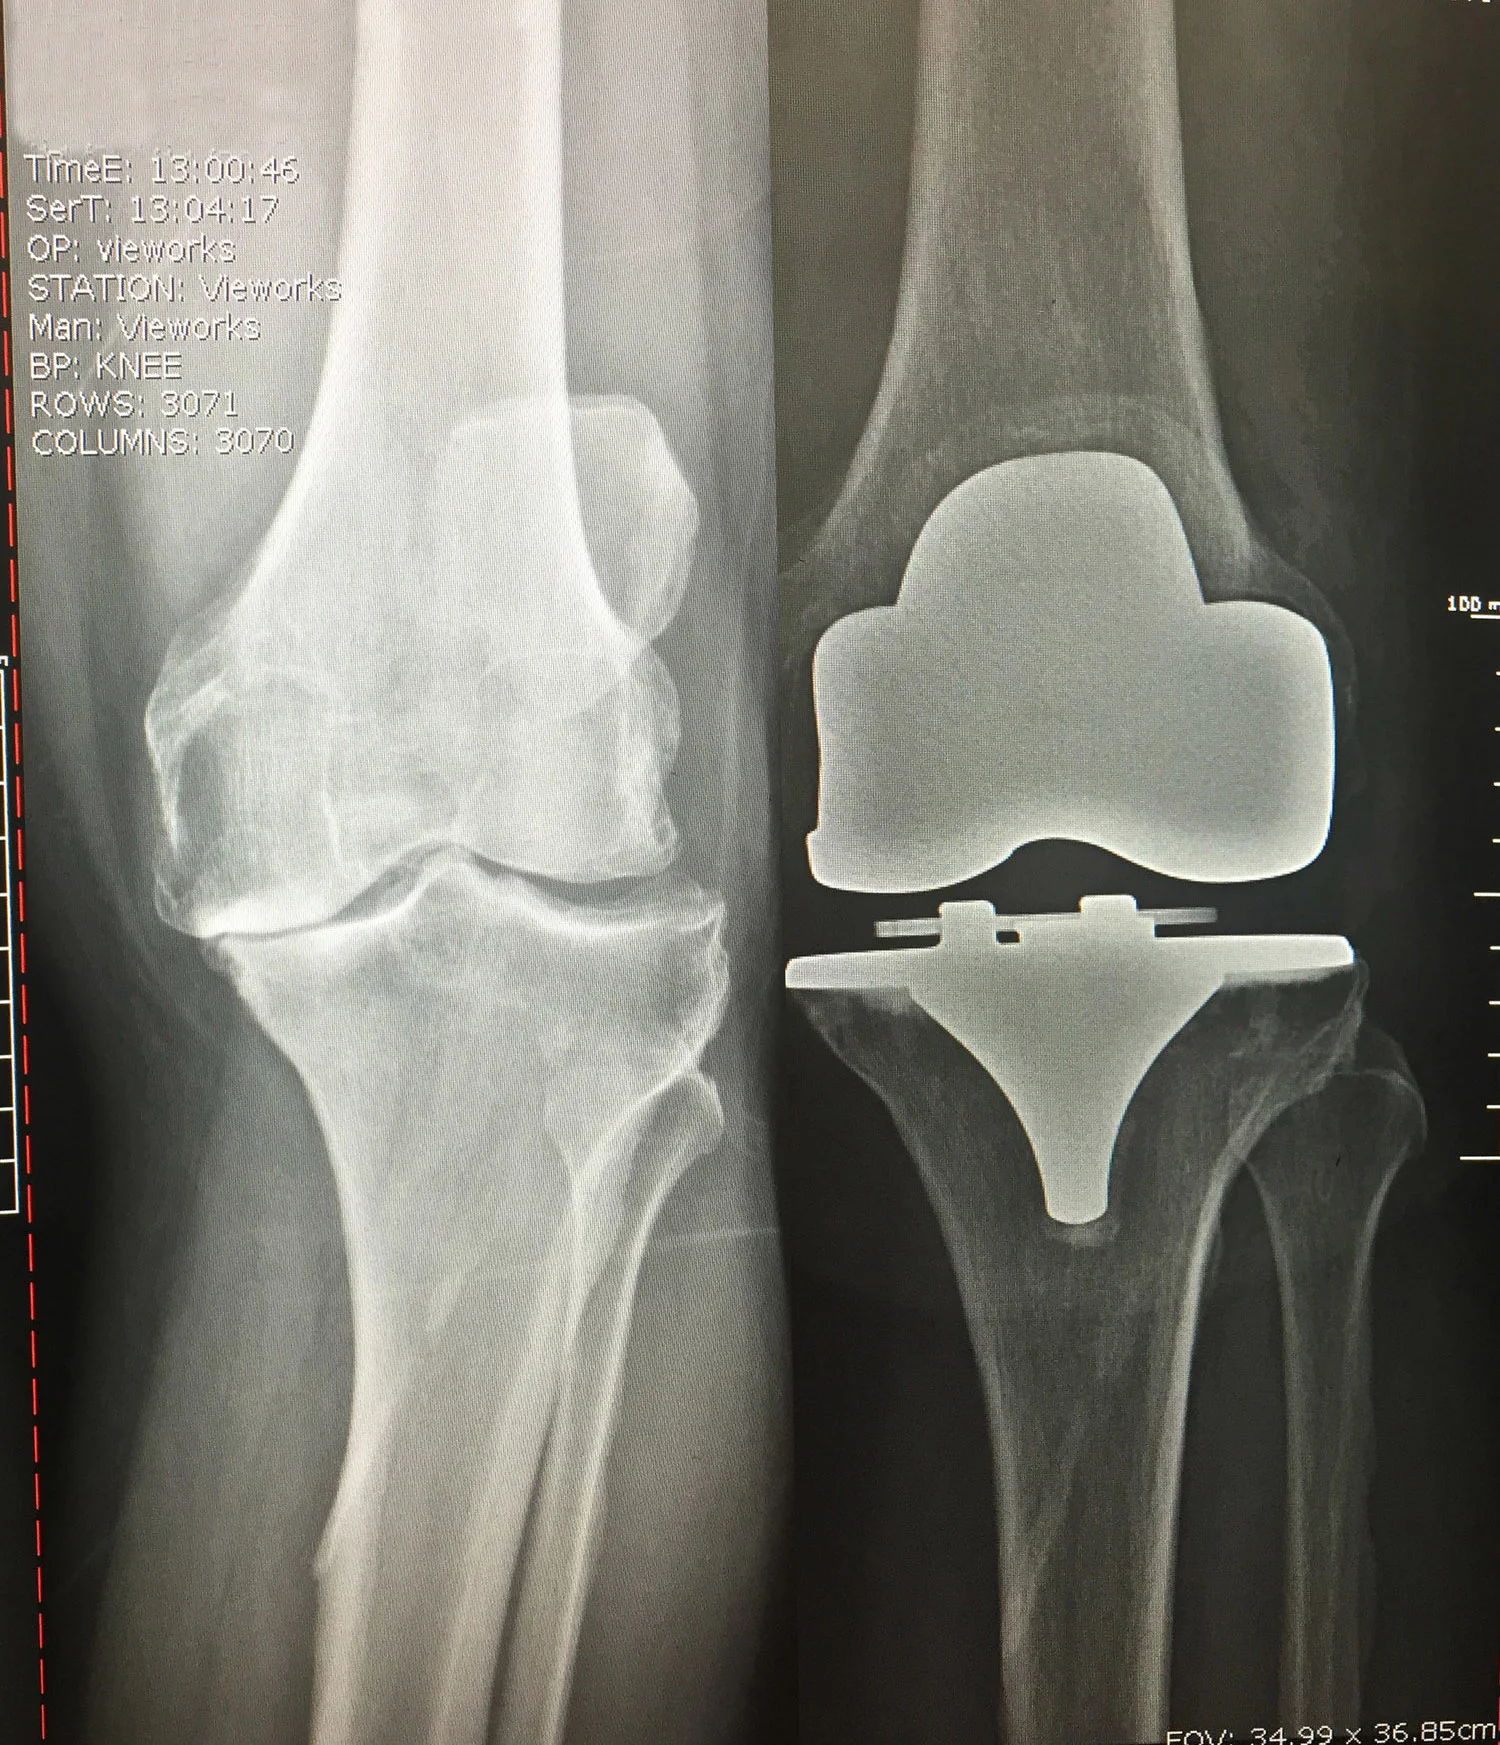

Before and After Knee X-Rays

Before: Bone on bone knee arthritis

After: Total Knee Replacement

BIOMET